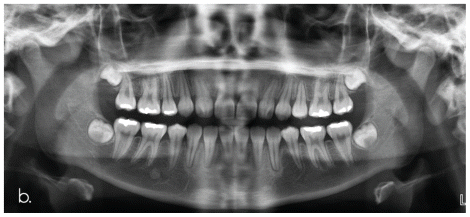

The diagnosis of resorption is usually an incidental radiographic finding and is difficult, as the affected teeth are often asymptomatic (35). The most common diagnostic method is panoramic radiography, either alone or in combination with periapical imaging, primarily to overcome diagnostic difficulties in the anterior region (36). In their study, Sameshima and Asgarifar, comparing panoramic radiographs with periapical images as a diagnostic tool, found that panoramic imaging overestimates resorption and root shortening by more than 20% (37). However, imaging with the paralleling technique, as reported by Remington et al., cannot accurately measure root lengths (38). Furthermore, although it has high diagnostic value, it is geometrically inaccurate (39).

To investigate the morphology and extent of resorption on all root surfaces, the MBD method proposed by Gartner et al. is often used, which involves taking two radiographs—one perpendicular to the root and the other with mesial angulation (7). The different imaging angles help identify the surfaces involved and allow proper classification of the lesion. Nevertheless, in their study, Creanga et al. observed slightly better diagnostic outcomes (40) using only perpendicular projections compared with angled projections. The available literature, however, is limited, as all studies comparing two-dimensional with three-dimensional imaging treat periapical radiography as a single modality regardless of the angle at which it is taken (40).

The above study agrees that the most reliable diagnostic method for resorption is three-dimensional imaging. CBCT imaging is a more sensitive technique, although its reported sensitivity is 69% (41).

The specificity of the method using different angulations of conventional periapical radiographs and CBCT was found to be above 79%, with that of CBCT reaching 91% (40).

Patel et al. support the use of cone-beam computed tomography, as it appears to have greater diagnostic value—something that is now also recommended by the European Society of Endodontology (32).

Regarding external apical resorption, in two-dimensional imaging, it appears as shortening and rounding of the apex with well-defined margins and the presence or absence of a periapical lesion, depending on whether an inflammatory cause is present. The root canal remains clearly visible and continuous. In three-dimensional imaging (CBCT), the authors describe asymmetry at the apex, conical loss of tooth structure, or a crater-like defect, with or without bone involvement, depending on the presence of an inflammatory etiology. When the cause is orthodontic treatment, multiple teeth are symmetrically affected.